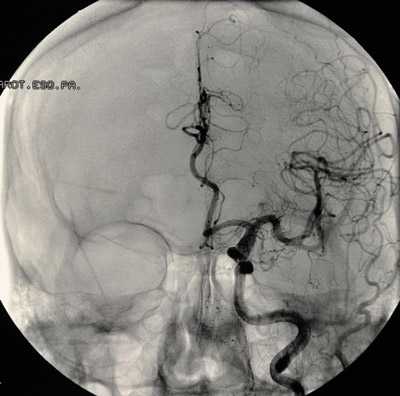

Перед планированием операции больной подвергается всевозможным обследованиям, включая анализы крови, мочи, коагулограмму, кардиограмму и т. д., как и при других оперативных вмешательствах. Для локализации и уточнения характера сосудистого образования проводят КТ, МРТ с контрастированием, ангиографию, ультразвуковое исследование с допплером.

В случае разорвавшихся аневризм больной поступает в стационар с клиникой острого субарахноидального или внутримозгового кровоизлияния и направляется в нейрохирургическое отделение, времени на обследования фактически нет, поэтому приходится ограничиваться минимумом, позволяющим определиться с расположением мальформации.